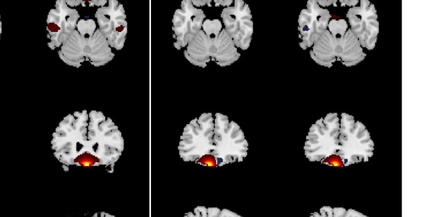

In the last two decades, unsupervised latent variable models---blind source separation (BSS) especially---have enjoyed a strong reputation for the interpretable features they produce. Seldom do these models combine the rich diversity of information available in multiple datasets. Multidatasets, on the other hand, yield joint solutions otherwise unavailable in isolation, with a potential for pivotal insights into complex systems. To take advantage of the complex multidimensional subspace structures that capture underlying modes of shared and unique variability across and within datasets, we present a direct, principled approach to multidataset combination. We design a new method called multidataset independent subspace analysis (MISA) that leverages joint information from multiple heterogeneous datasets in a flexible and synergistic fashion. Methodological innovations exploiting the Kotz distribution for subspace modeling in conjunction with a novel combinatorial optimization for evasion of local minima enable MISA to produce a robust generalization of independent component analysis (ICA), independent vector analysis (IVA), and independent subspace analysis (ISA) in a single unified model. We highlight the utility of MISA for multimodal information fusion, including sample-poor regimes and low signal-to-noise ratio scenarios, promoting novel applications in both unimodal and multimodal brain imaging data.